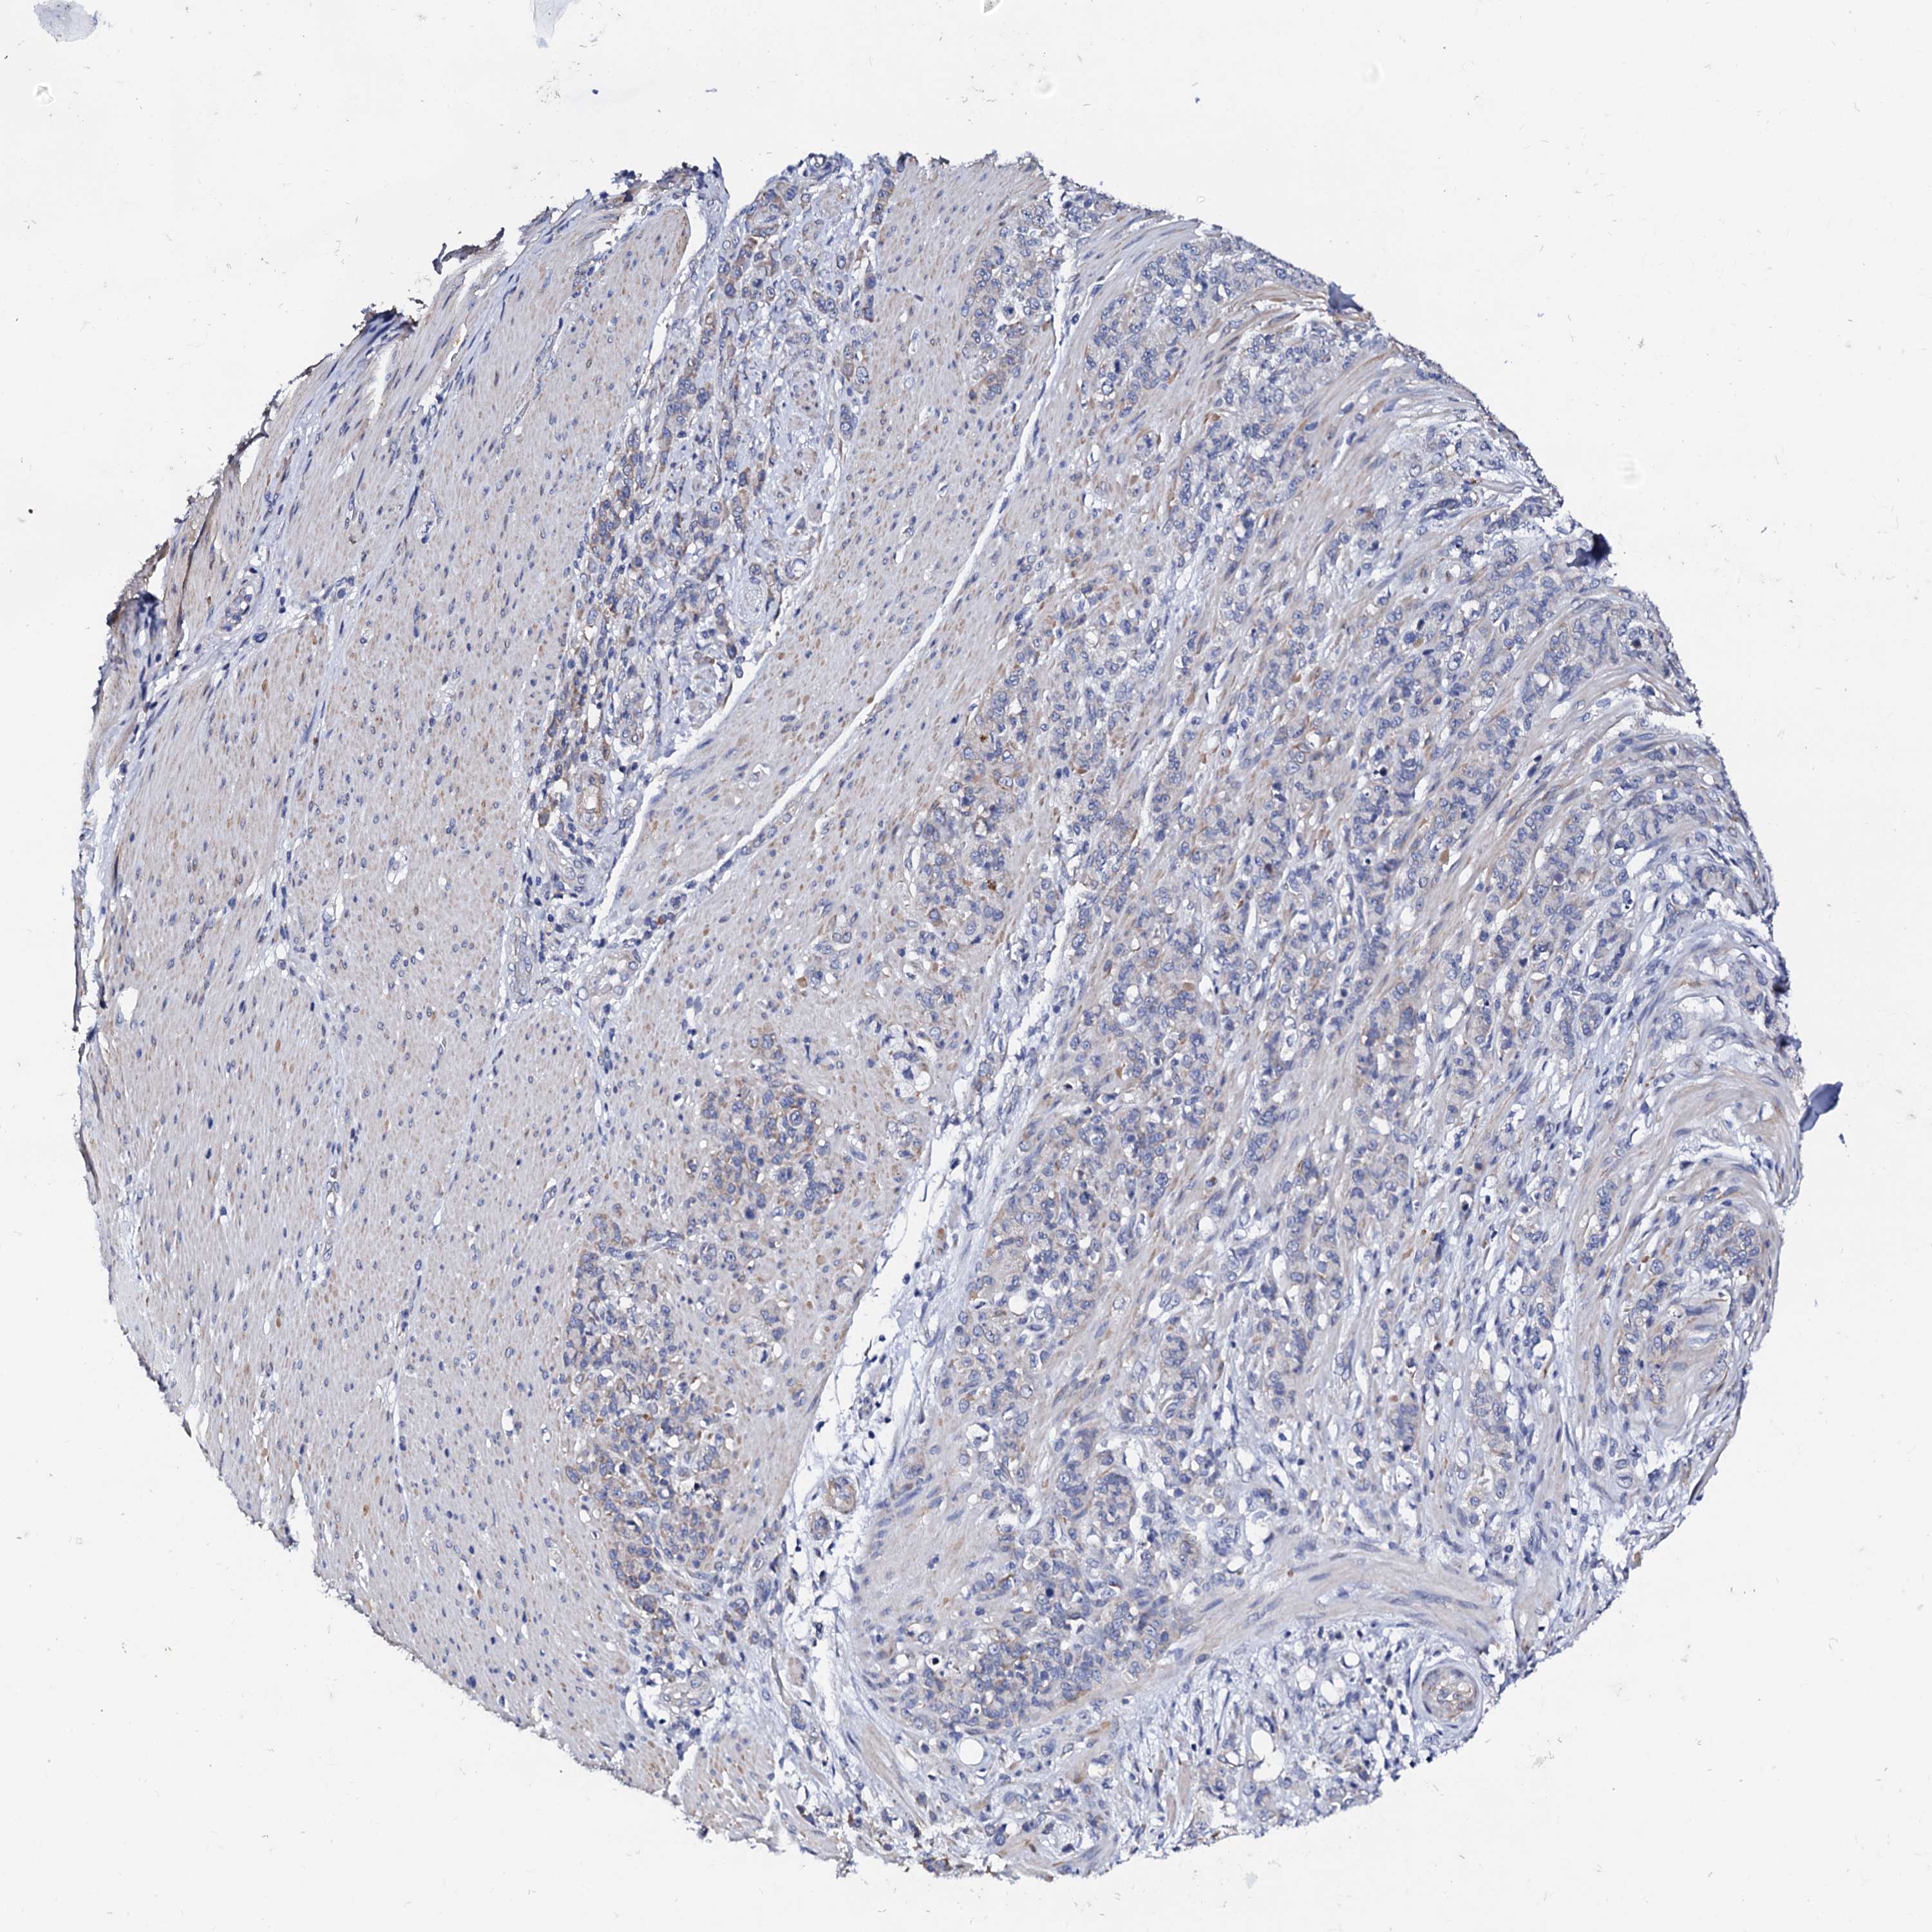

STOMACH CANCER - Protein expressioni

A mouse-over function shows sample information and annotation data. Click on an image to view it in a full screen mode. Samples can be filtered based on level of antibody staining by selecting one or several of the following categories: high, medium, low and not detected. The assay and annotation is described here.

Note that samples used for immunohistochemistry by the Human Protein Atlas do not correspond to samples in the TCGA dataset.

Antibody stainingi

Antibody staining in the annotated cell types in the current human tissue is reported as not detected, low, medium, or high, based on conventional immunohistochemistry profiling in selected tissues. This score is based on the combination of the staining intensity and fraction of stained cells.

Each image is clickable and will lead to virtual microscopy that enables deeper exploration of all samples and also displays staining intensity scores, fraction scores and subcellular localization as well as patient and tissue information for each sample.

Antibody HPA039360

Staining

High

Medium

Low

Not detected

Intensity

Strong

Moderate

Weak

Negative

Quantity

>75%

75%-25%

<25%

None

Location

Nuclear

Cytoplasmic/membranous

Cytoplasmic/membranous,nuclear

Adenocarcinoma, NOS